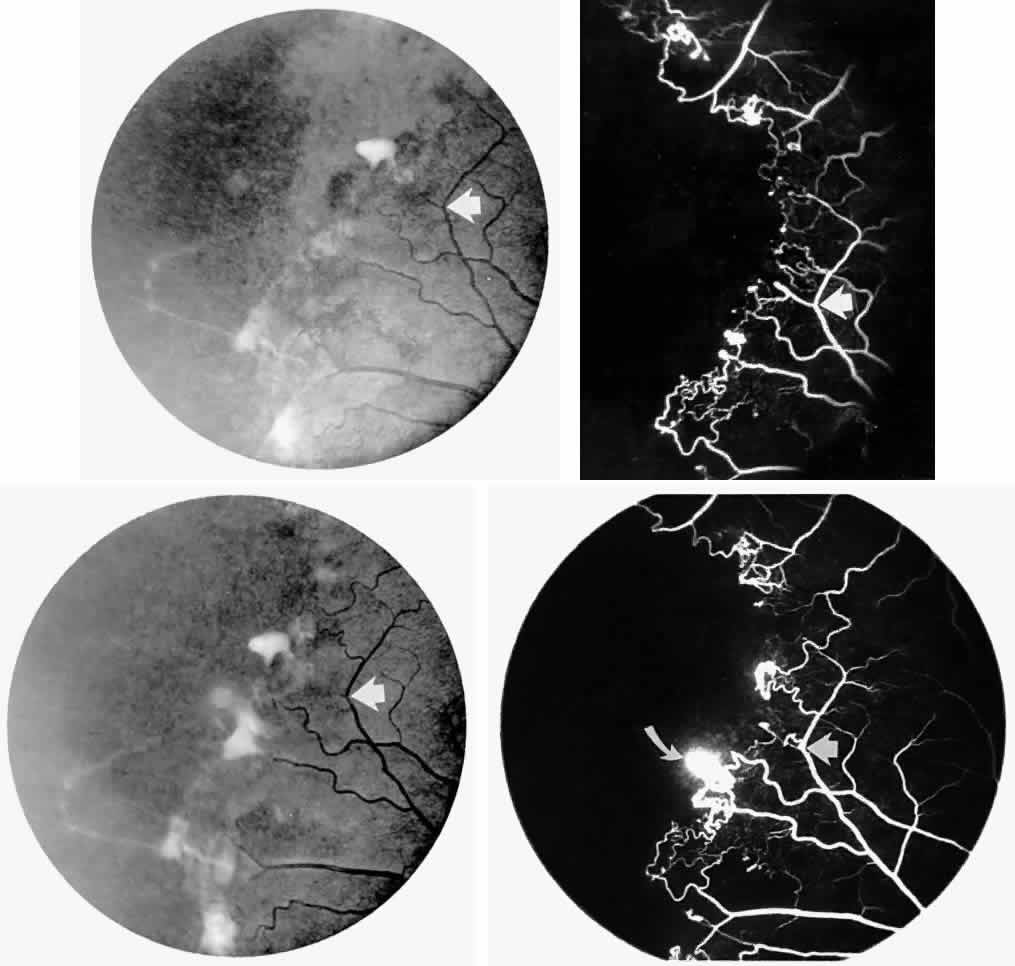

Occlusions of the fine vasculature of the macular and perimacular area have been reported in 10% to 40% of patients with sickle cell disease.18,83,91–99 In the acute phase, the occluded vessel will have a dark red appearance and may appear as a dark line on fluorescein angiography (Fig. 9). Nerve fiber layer infarcts (cotton-wool spots) are seen (see Fig. 8D and E;Fig. 10).100

Fig. 9. A 27-year-old man with homozygous sickle cell anemia. A. Fluorescein angiogram of the right eye shows multiple arteriolar occlusions temporal to the fovea (arrows). B. Same area 6 months later shows more extensive occlusions. The black arrowheads (A and B) identify corresponding arteriolar bifurcation.

Fig. 10. A 33-year-old woman with SC disease and stage III sickle cell retinopathy. A. Photograph of the right eye shows a cotton-wool spot with a dark segment identifying the occluded vessel (arrow). B. Fluorescein angiogram demonstrates nonfilling of the occluded vessel (arrow). C. Eighteen months later, the occluded vessel is still visible (arrow). D. Fluorescein angiogram demonstrates that there is still nonfilling of the vessel (arrow).

Other macular and perimacular changes include microaneurysm-like dots, dark and enlarged segments of arterioles, hairpin-shaped venular loops, pathologic avascular zones, and widening and irregularities of the foveal avascular zone (Figs. 11 and 12). In the Jamaican cohort study evaluating children with homozygous sickle cell anemia and SC disease between the ages of 5.0 and 7.5 years of age, no pathologic avascular zones could be identified despite a high incidence of peripheral vascular closure.31 In evaluating patients with homozygous sickle cell anemia, no relationship between ISC counts and macular abnormalities or visual acuity could be found.101 Using fluorescein angiography, investigators have found the foveal avascular zone to be significantly larger in eyes with clinical evidence of sickle cell maculopathy as compared with normal eyes and eyes without clinical evidence of sickle cell maculopathy.102–104

Careful examination by fluorescein angiography, looking for areas of capillary dropout and other capillary abnormalities, is often necessary to identify the macular changes. These changes may be transient, and the macula may appear normal on subsequent fluorescein angiograms (Fig. 13). Although fluorescein angiography may or may not demonstrate reperfusion of a previously occluded capillary bed, a loss of the inner retinal layers results in an ophthalmoscopic focal concavity with an abnormal reflex (retinal depression sign) (see Fig. 8E).105,106 These changes are usually permanent. The retinal depression sign is not pathognomonic of sickle cell disease and may be seen with other arteriolar occlusive diseases, such as embolic retinopathy, vasculitis, and hypertension.

Fig. 13. A. A 32-year-old man with homozygous sickle cell anemia and proliferative sickle retinopathy. A fluorescein angiogram shows temporal occlusions and a pathologic avascular zone (PAZ) temporal to the foveal avascular zone. B. Seven years later, there is filling of the previously noted PAZ.